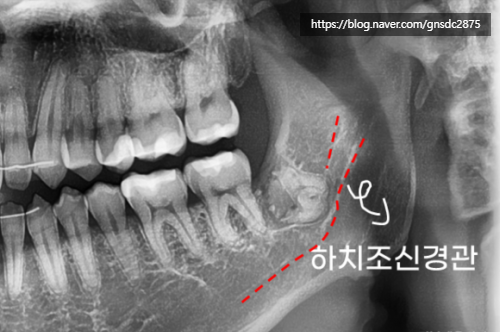

타치과에서 사랑니 발치를 하다 신경관이 가까워

뿌리를 남긴 채로 마무리하신 분입니다.

표시한 곳에 뿌리가

신경관가 가깝게 위치하여 남아있는 것이 보입니다.